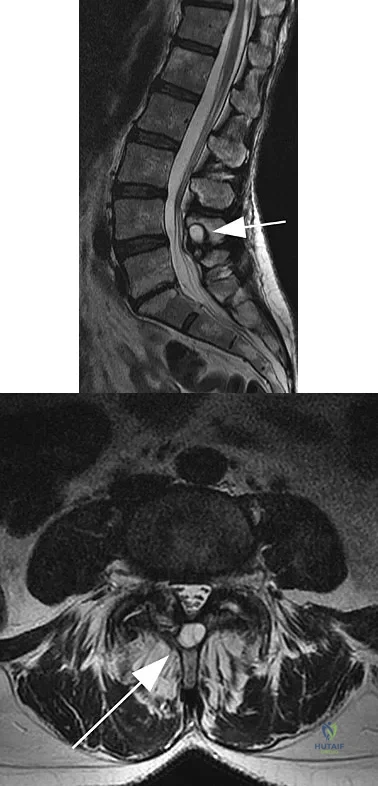

Figures 11a and 11b show the T2-weighted MRI scans of the lumbar spine of a 53-year-old woman who has low back and right lower extremity pain. What structure is the arrow pointing to in Figure 11a?

A 42-year-old woman who has had an 18-month history of severe low back pain is referred to your office for surgical evaluation. She reports that the pain initially began with right lower extremity pain and management consisted of oral analgesics, nonsteroidal anti-inflammatory drugs, and muscle relaxants. She has seen a chiropractor as well as a pain management specialist and she is status-post epidural steroid injections. She has also completed exhaustive physical therapy, as she is a certified athletic trainer and runs a health fitness program at a community hospital. Currently, she denies lower extremity pain and her pain is isolated to her low back and is subjectively graded as 8/10, with 10 being the worst pain she has ever experienced. The pain is interfering with her activities of daily living and she is seeking definitive treatment. Figures 32a through 32c show current MRI scans. Based on the current available medical literature, what is the most appropriate treatment?